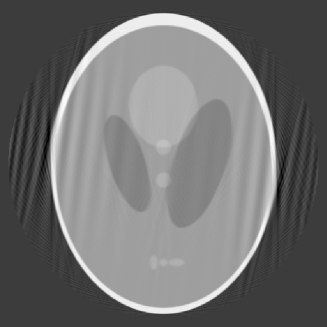

In our first example, , which amounts to data limited in an angle of about ; in other words, views from about angle are missing. The reconstruction by our algorithm is given in Figure 3 in which and for the left figure and for the right figure.

The left image is reconstructed with and ; it is a fairly accurate reconstruction, although there are noticeable artifacts in the direction of missing views and a bit distortion around two spots on the edges. The right image is reconstructed with and ; it shows clearly artifacts of ripples, but the image appears to be sharper and has less distortion than the one in the left otherwise. In the case of , the maximum of the condition numbers of the matrices is 160, so that the matrices are rather well conditioned. In the case of , the maximum of the conditions numbers is , which may have contributed to the ripples in the image.

The condition that guarantees the non-singularity of the matrices in this case is , whereas our computation of eigenvalues shows that has to be much smaller in order that the matrices are well conditioned. For our other examples, we will mostly take . The choice of means that our sampling of coefficients follows a curve that decreases from 1 to 0.9, a decline that is rather mild, which leads to reasonable reconstruction image.